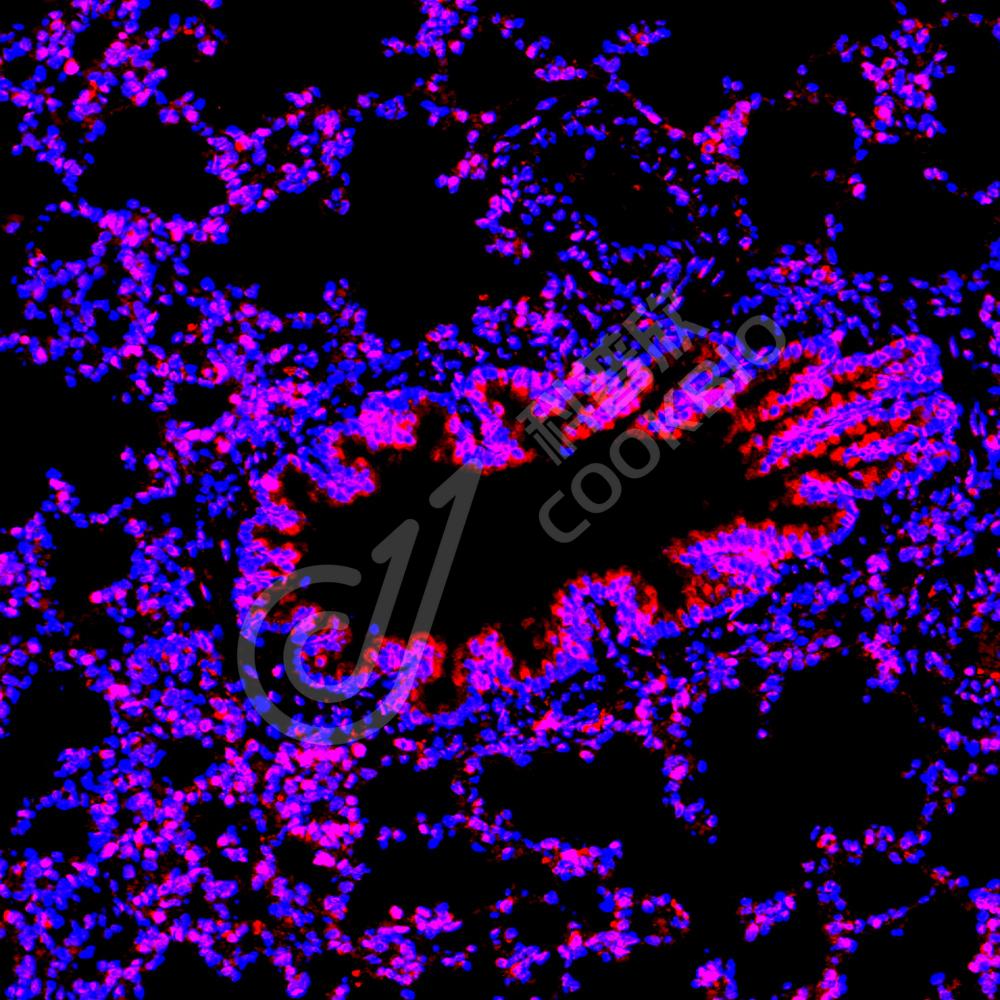

IF检测TPX2蛋白(货号 K1338109)(红色).

样品: 人肺癌, 4%多聚甲醛 (货号KSG1101) 固定12-24小时.

抗原修复: Tris-EDTA抗原修复液(pH 9.0) (KSG1203), 98℃, 20分钟.

封闭: 3% BSA(货号KSGC305010)的PBS溶液, 室温孵育30分钟.

—抗: 1: 700稀释, 4℃ 孵育过夜.

二抗: Cy3标记山羊抗兔IgG (H+L) (货号KB63909), 1: 300稀释, 室温孵育1小时.